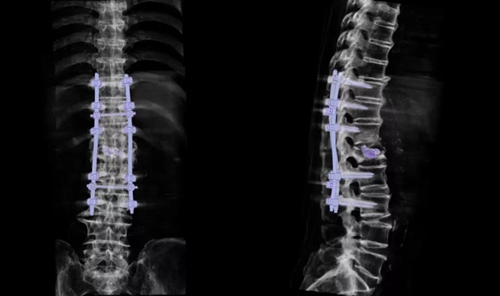

靳安民教授在详细了解薛大爷情况后,制定了创伤较小的手术方式,决定采用:后路脊柱内固定+病灶清除,为薛大爷进行治疗。

靳安民教授从侧后方入路清除病灶组织,相比从侧前方入路减少了一条切口,大大减小手术创伤,术中采用肌间隙入路安置椎弓根螺钉,大大减少对周围软组织的损伤。

2小时后手术顺利完成了,出血不到100ml。